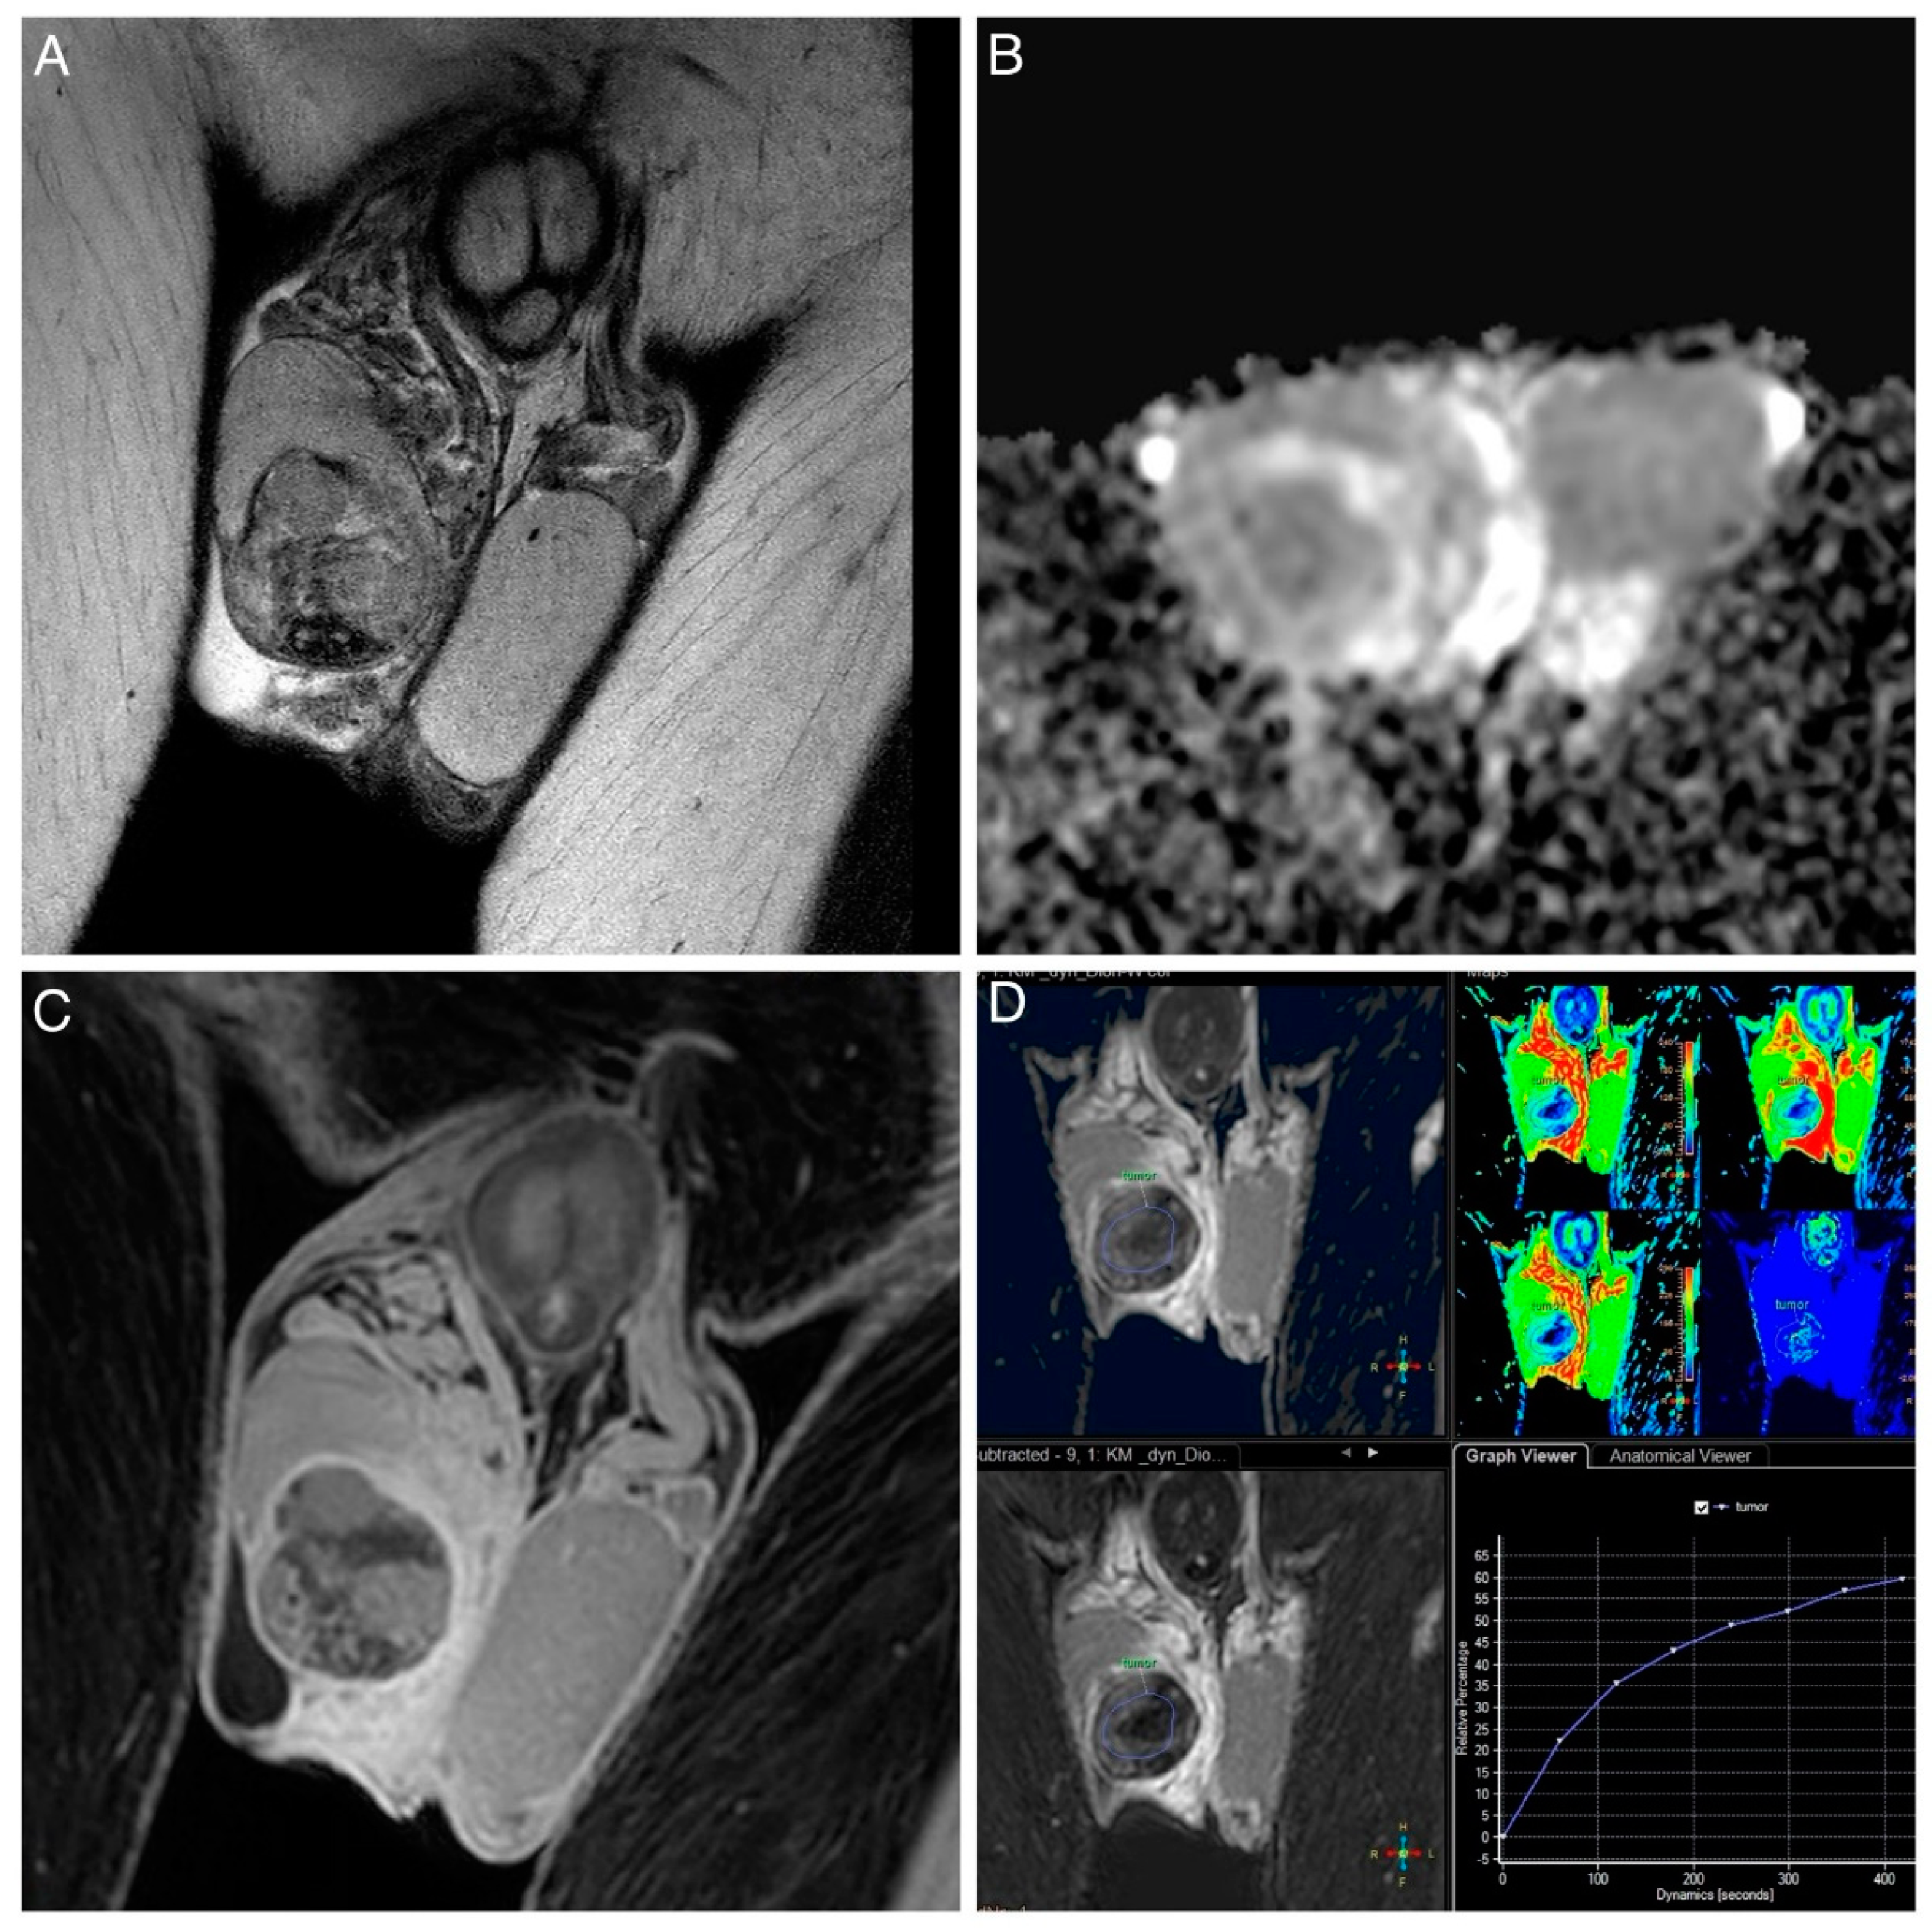

| Type of contrast enhancement (compare [20]) | n absence of enhancement/Type 0 curve (%) | 3 (25.0) | 1 (2.9) | p = 0.025 * |

| n Type I curve (%) | 2 (16.7) | 10 (28.6) | ||

| n Type II curve (%) | 2 (16.7) | 17 (48.6) | ||

| n Type III curve (%) | 5 (41.7) | 7 (20.0) | ||

| Pattern of contrast enhancement | n homogenous (%) | 6 (66.7) | 5 (14.3) | p = 0.005 ** |

| n heterogenous (%) | 2 (22.2) | 22 (62.9) | ||

| n rim-like (%) | 1 (11.1) | 8 (22.9) | ||

| T1 signal | n predominantly low (%) | 2 (16.7) | 3 (8.6) | 0.387 1 |

| n isointense (%) | 10 (83.3) | 30 (85.7) | ||

| n predominantly high (%) | 0 (0) | 2 (5.7) | ||

| T2 signal | n predominantly low (%) | 6 (50.0) | 25 (71.4) | 0.148 2 |

| n isointense (%) | 1 (8.3) | 5 (14.3) | ||

| n predominantly high (%) | 4 (33.3) | 5 (14.3) | ||

| n no signal (%) | 1 (8.3) | 0 (0) | ||

| Presence of enhancing intra-tumoral septa | n Yes (%) | 2 (16.7) | 17 (48.6) | p = 0.087 3 |

| n No (%) | 10 (83.3) | 18 (51.4) | ||

| Presence of areas of hemorrhage (= T1 hyperintensity) | n Yes (%) | 0 (0) | 5 (14.3) | p = 0.309 3 |

| n No (%) | 12 (100) | 30 (85.7) | ||

| Presence of areas of necrosis (= T2 hyperintensity) | n Yes (%) | 2 (16.7) | 9 (25.7) | p = 0.703 3 |

| n No (%) | 10 (83.3) | 26 (74.3) | ||

| Presence of calcification | n Yes (%) | 1 (8.3) | 4 (11.4) | p > 0.999 3 |

| n No (%) | 11 (91.7) | 31 (88.6) | ||

| Presence of ipsilateral hydrocele | n Yes (%) | 10 (83.3) | 19 (54.3) | p = 0.095 3 |

| n No (%) | 2 (16.7) | 16 (45.7) | ||

| Smooth tumor margins | n Yes (%) | 11 (91.7) | 22 (62.9) | p = 0.077 3 |

| n No (%) | 1 (8.3) | 13 (37.1) | ||